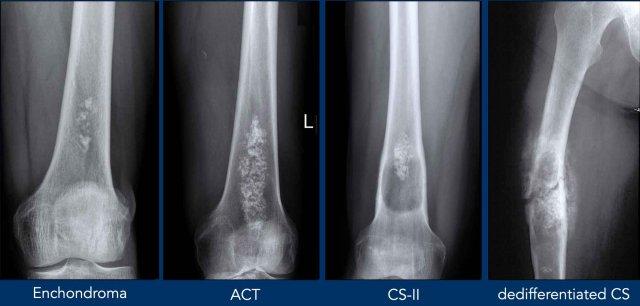

Thuật ngữ trong U Sụn Xương

Hình này minh họa các ví dụ để giải thích thuật ngữ dùng để mô tả u sụn xương.

Trong một số ví dụ, có thể có nhiều hơn một dấu hiệu điển hình.

- Vôi hóa dạng bỏng ngô (Popcorn)Thường gặp trong các u sụn xương.

- Hình gợn sóng vỏ xương (Scalloping) đề cập đến sự tiêu xương lớp trong của vỏ xương do một tổn thương phát triển chậm. Thường gặp nhất trong u nguyên bào sụn không điển hình (ACT), nhưng cũng có thể xuất hiện trong loạn sản xơ, u tế bào khổng lồ của xương hoặc bệnh mô bào Langerhans.

- Giãn rộng xương (Expansion)có nghĩa là xương bị giãn rộng. Có thể xảy ra trong ACT nhưng là dấu hiệu đáng lo ngại của ung thư sụn xương độ cao hơn.

- Phản ứng màng xương (Periostitis) hay phản ứng màng xương là một dấu hiệu điển hình trong sarcoma sụn độ cao, tuy nhiên nó có thể xuất hiện sau gãy xương trong u sụn nội xương (enchondroma) hoặc khối u sụn không điển hình (ACT). Đôi khi phản ứng màng xương chỉ có thể nhìn thấy trên MRI qua một viền tăng tín hiệu T2 và ngấm thuốc xung quanh vỏ xương.

- Phá hủy vỏ xương (Cortical destruction) có nghĩa là khối u phát triển xâm lấn cục bộ qua vỏ xương. Đây là dấu hiệu điển hình trong chondrosarcoma độ cao

- Lấp đầy từ vách tới vách (Wall to wall filling) có nghĩa là tổn thương lan rộng từ

vỏ xương phía trước đến phía sau hoặc từ vỏ xương phía trong đến phía ngoài. Cũng cần lưu ý tình trạng dày vỏ xương. - Ngấm thuốc vòng-vách-nốt (Rings-and-arcs enhancement)là kiểu ngấm thuốc điển hình của u sụn xương, giúp bác sĩ CĐHA đưa ra chẩn đoán đúng.

- Tiêu xương (Osteolysis) có nghĩa là trong một khối u sụn có vùng thấu quang không có vôi hóa chất nền. Điều này có thể do thành phần nhầy trong CS độ cao. Vùng này tăng tín hiệu trên các chuỗi xung nhạy cảm với dịch có ức chế mỡ và không ngấm thuốc tương phản.

- Mỡ xen kẽ (Interspersed fat)thường

hiện diện trong các khối u sụn vỏ thượng thận (ACTs) giữa các nốt sụn. Theo thời gian, các nốt sụn

có thể giảm dần khi lượng mỡ xen kẽ tăng lên.

X-ray

Trên phim X-quang, u sụn xương thể hiện các ổ vôi hóa nền chất dạng nốt, giống hình bỏng ngô.

Các vôi hóa này có thể xuất hiện trên toàn phổ của u sụn xương.

Often the tumor

size is underestimated on a radiograph, as frequently only the mineralized part of the

tumor is visible.